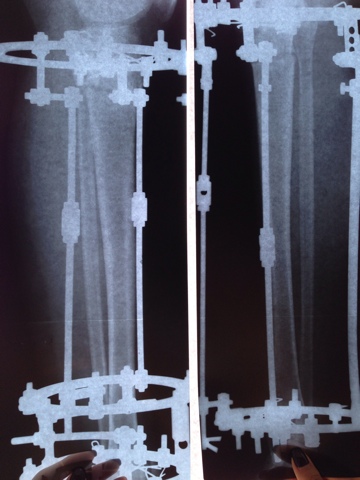

Рентген в 2 месяца с момента операции.

image-15-05-14-16-03-3.jpeg

image-15-05-14-16-03-2.jpeg